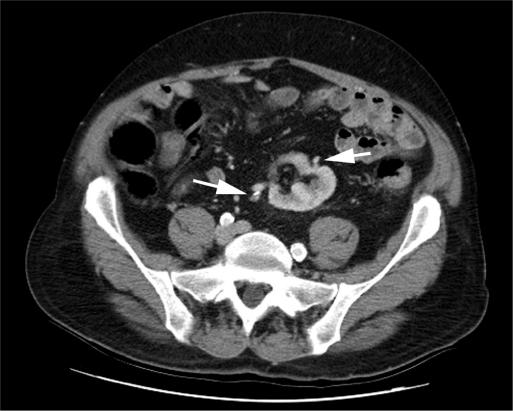

A 64-year-old male with a history of end-stage renal disease was diagnosed with a 2.6-cm enhancing mass in a pelvic left kidney with 2 separate sources of blood supply. He was offered either an open radical nephrectomy or a laparoscopic radical nephrectomy and opted for the minimally invasive approach.

The procedure was performed successfully without complications and with minimal blood loss. The case was marked both by difficulty in mobilizing the sigmoid colon and the limited working space of the pelvis, which made localization of the numerous hilar vessels challenging.

Laparoscopic radical nephrectomy for a pelvic ectopic kidney appears to be safe and efficacious. Success is dependent on familiarity with pelvic anatomy, optimal port placement, and preprocedure knowledge of the often-complicated vascular anatomy of the ectopic kidney. Preoperative imaging to delineate anomalous vascular anatomy is mandatory, and ureteral catheter placement is helpful for intraoperative identification purposes.